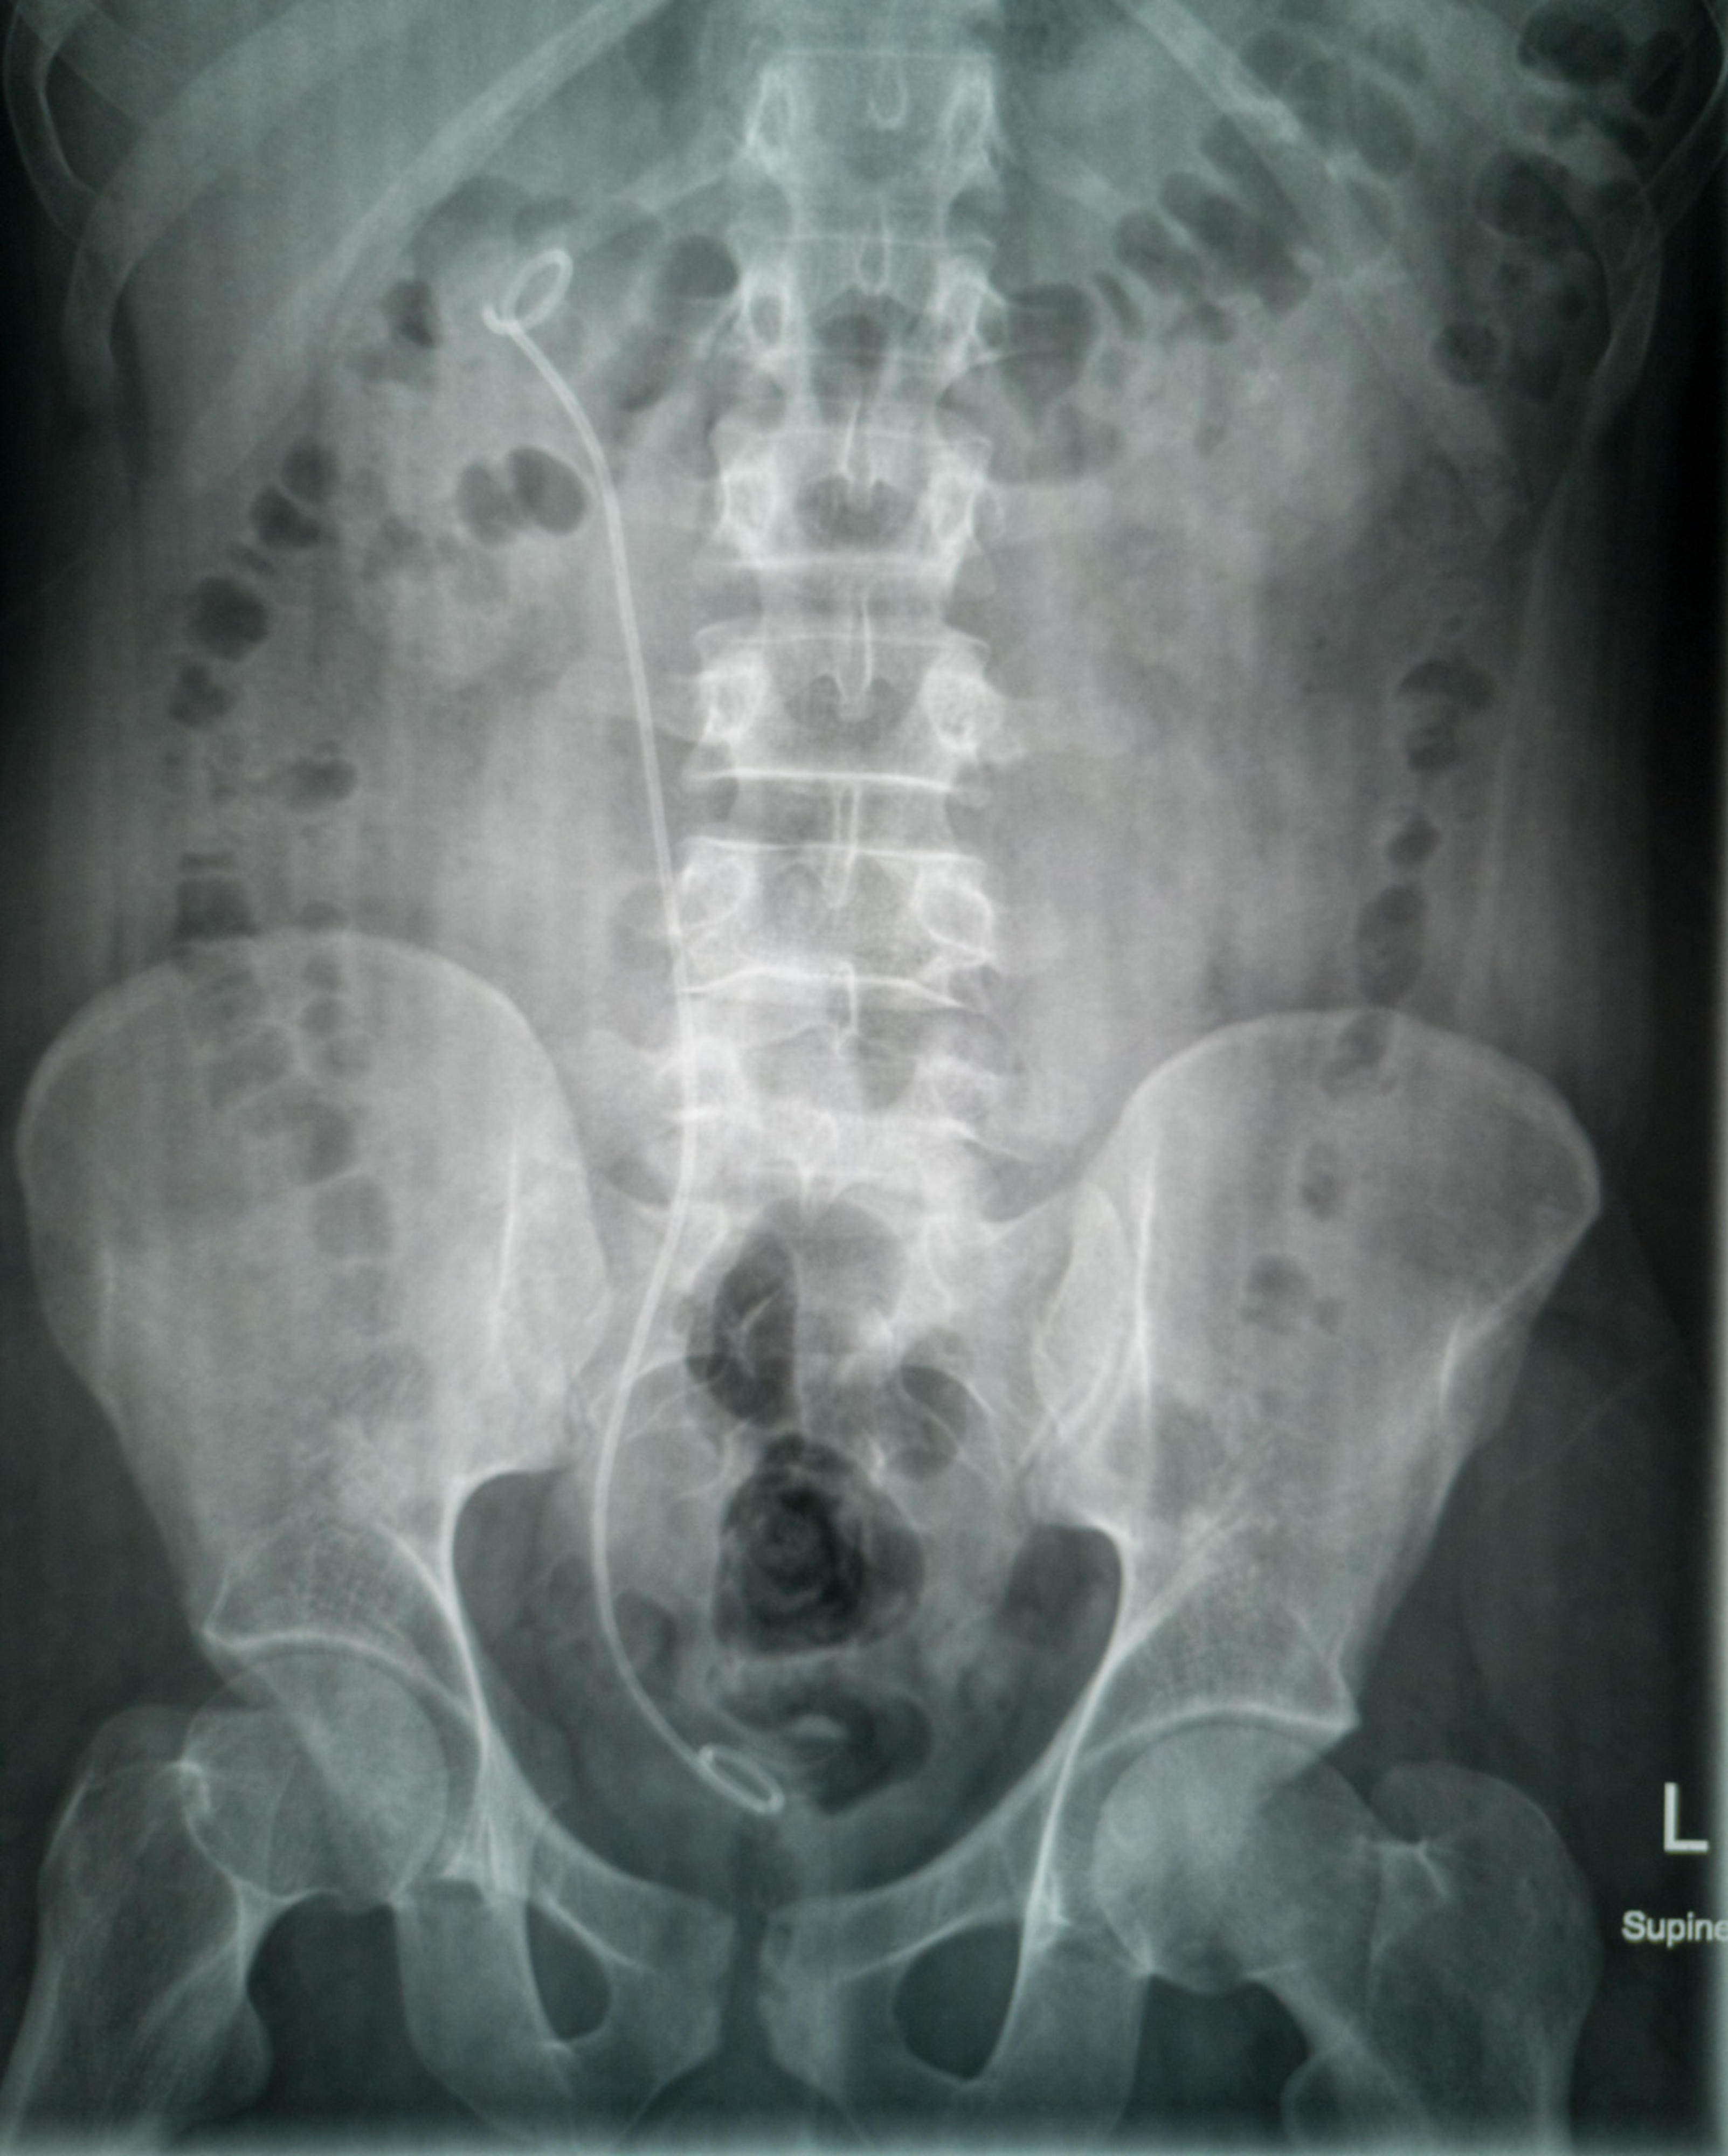

Stent i urinledaren

I en akut situation som orsakas av urinledarsten blir man ibland tvungen att placera en tunn plastslang (stent) för att trygga flödet av urin från njurbäckenet till urinblåsan. Ingreppet görs som endoskopi genom urinröret. Ingreppet görs på jouren, antingen i operationssalen eller på polikliniken. Om stenen inte avlägsnas av sig själv bredvid stenten, avlägsnas den senare med ett endoskopiskt ingrepp.

Om det finns mycket stensmulor, placeras ett plaströr, en stent, mellan njurbäckenet och urinblåsan, eftersom en riklig stenmassa ibland kan täppa urinledaren. Stenten avlägsnas senare under ett poliklinikbesök.